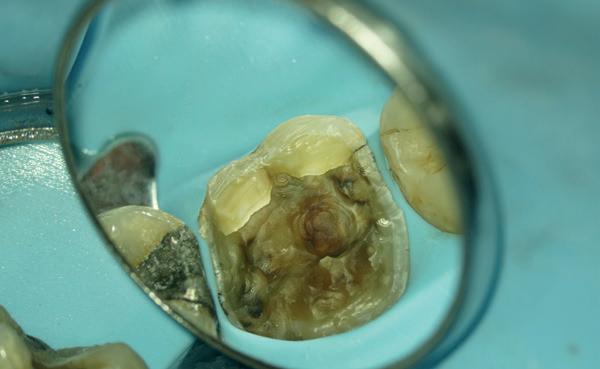

Deze 51-jarige vrouw werd verwezen omwille van pijnklachten met de vraag of een wortelkanaalbehandeling nog mogelijk was, of dat er eerder naar extractie gekeken moest worden (foto 7). De tand testte nog vitaal tijdens de consultatie dus ik besloot om eerst de vulling te verwijderen. Het bleek een typische “cracked tooth” (foto 8-9). Ik besloot om de tand te voorzien van een adhesieve stompopbouw (foto 10). En bij de opvolging zes maanden later (foto 11) was de patiënt al die tijd klachtenvrij en kreeg de tandarts groen licht om verder te gaan met een indirecte restauratie. Geen wortelkanaalbehandeling en al zeker geen extractie nodig.

Elke tandarts kent het. Je hebt een endostart uitgevoerd, maar een week later komt de patiënt weer terug met klachten. Het ging de goede kant op, maar na een paar dagen kwam de pijn toch weer opzetten. ‘’Raar, ik weet toch zeker dat ik alle kanalen netjes heb gereinigd’’, denk je dan bij jezelf. Het is een soort gemeengoed geworden, om de patiënt dan tussendoor te laten komen zodat de kanalen weer gedesinfecteerd kunnen worden met natriumhypochloriet. Maar is dat wel doeltreffend? Waarom zijn die bacteriën zo snel weer van betekenis geworden? Graag leg ik kort uit hoe je deze situatie kunt voorkomen aan de hand van een eenvoudige casus uit de praktijk.

Een 58-jarige patiënt was naar onze praktijk verwezen door zijn eigen tandarts. Hij had pijn en een flinke zwelling aan element 35. Zijn tandarts had een nette endodontische opening gemaakt en het element ontdaan van al het geïnfecteerde en/of necrotische pulpaweefsel en het kanaal uitvoerig gedesinfecteerd.

Aanvankelijk ging het goed, maar na een paar dagen kwam de patiënt toch weer terug met een flinke zwelling. Ondanks herhaalde behandelingen kwam de klacht net zo hard weer terug. Dit proces heeft zich wel zes keer herhaald, zonder resultaat.

Wat direct opviel aan de meegestuurde röntgenfoto was de matige coronale restauratie. De lekkende vulling zou het pijnlijke proces dat meneer heeft doorgemaakt verklaren. Bij het spoelen van het wortelkanaalstelsel wordt dan weliswaar veel gedesinfecteerd, maar binnen de kortste keren stromen de bacteriën en het substraat via de lekkage onder de vulling doodleuk weer naar binnen!

Naast de matige restauratie kon ik verder geen open apex, verticale fractuur of een andere oorzaak ontdekken, waardoor de bacteriën in het element zich in rap tempo konden vermenigvuldigen.

Om te voorkomen dat er niet wéér een infectie plaatsvindt, heb ik tijdens het eerste consult niet alleen het wortelkanaalstelsel gedesinfecteerd, maar ook direct de coronale restauratie vervangen.

Het is daarbij belangrijk om voldoende tijd in te plannen. Plan maar gerust 45 minuten in. Er zit op dat moment niets anders op dan wat ruimte te laten creëren in je agenda. Dat periodieke consult of die vulafspraak kan wel wachten. Als je duidelijk uitlegt dat jij hiermee voldoende tijd krijgt om een andere patiënt uit de brand te helpen, dan zullen de meeste mensen hier begrip voor hebben.

Na de eerste behandeling was en bleef meneer klachtenvrij en konden wij rustig de endodontische behandeling verder inplannen en afronden.

Samenvattend

Wees altijd kritisch op de coronale restauratie! Heeft de patiënt geen klachten meer gehad sinds het uitvoeren van de endostart? Dan is dit een teken dat de coronale restauratie voldoet.

Zijn de klachten wel teruggekomen of niet volledig verdwenen? Probeer dan te achterhalen waarom dit zo is. De kans is groot dat de kroon of vulling lekt of los zit.

Het vervaardigen van een niet lekkende coronale restauratie voorkomt trouwens niet alleen dat de pijnklacht op korte termijn terugkomt, maar zorgt er ook voor dat de prognose van de wortelkanaalbehandeling aanzienlijk verbetert.

Ik verwijs daarom vaak naar de systematic review en meta-analyse van Gillen et al. (2011), waarin duidelijk naar voren is gekomen dat een adequate coronale restauratie minstens zo belangrijk is als een correct uitgevoerde wortelkanaalbehandeling.